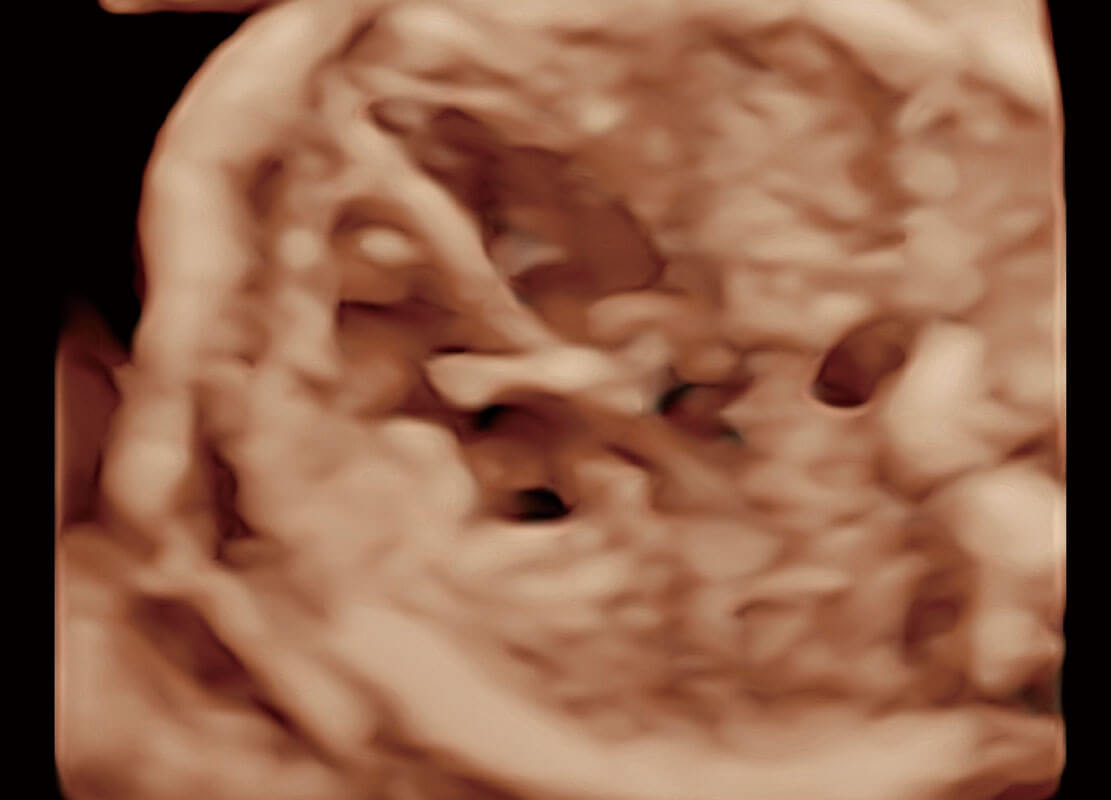

• 腔内三维-宫内节育器

• 腔内三维-光影成像

• 高分辨率容积成像-早孕胎儿

• 光影成像-孕囊